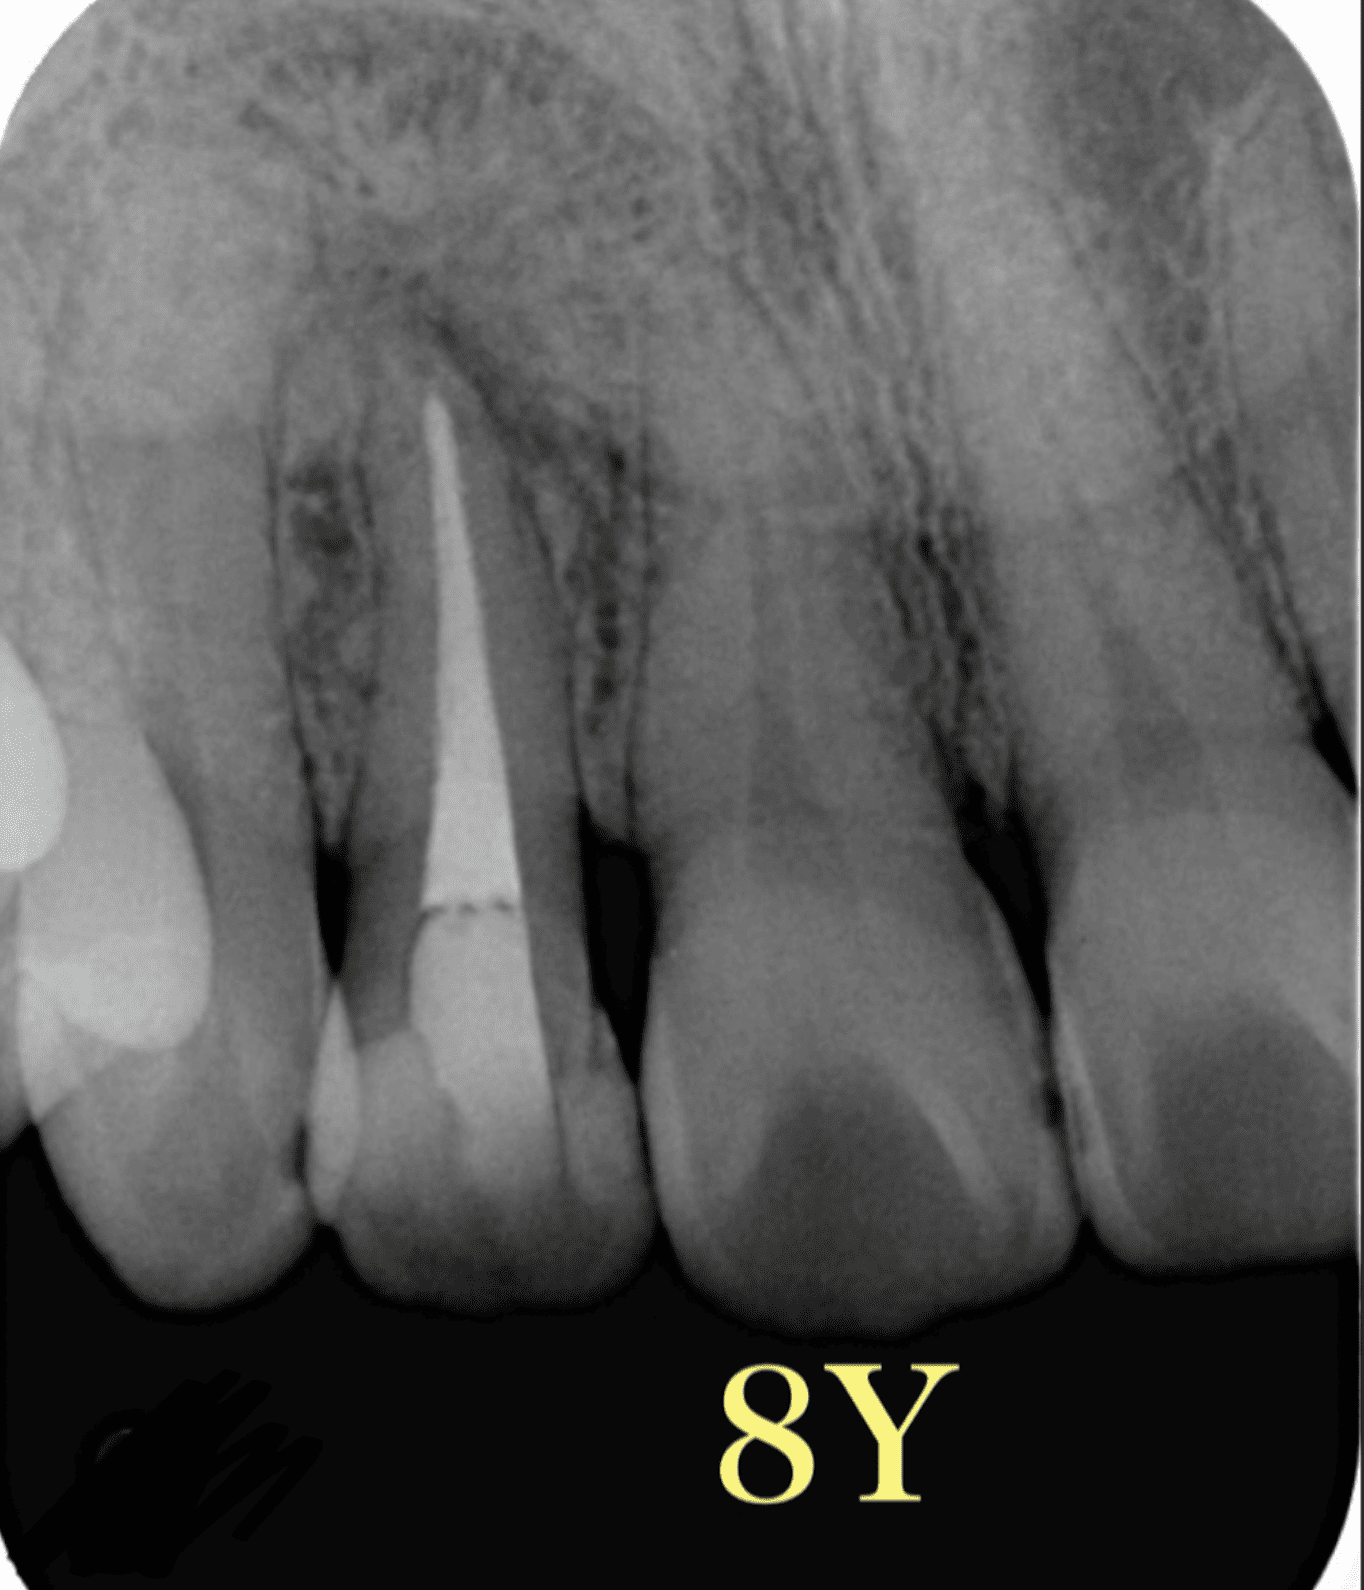

• 再根管治療8年後の経過

再根管治療8年後の経過